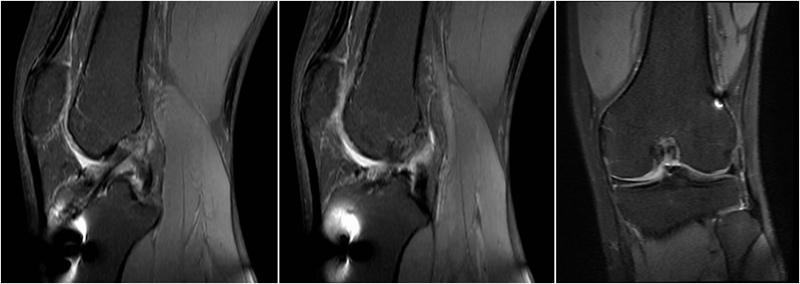

术前MRI

术后MRI

MRI检查评估ACL-R术后——韧带连续性信号好、方向好、愈合快,没有Cyclops综合征。